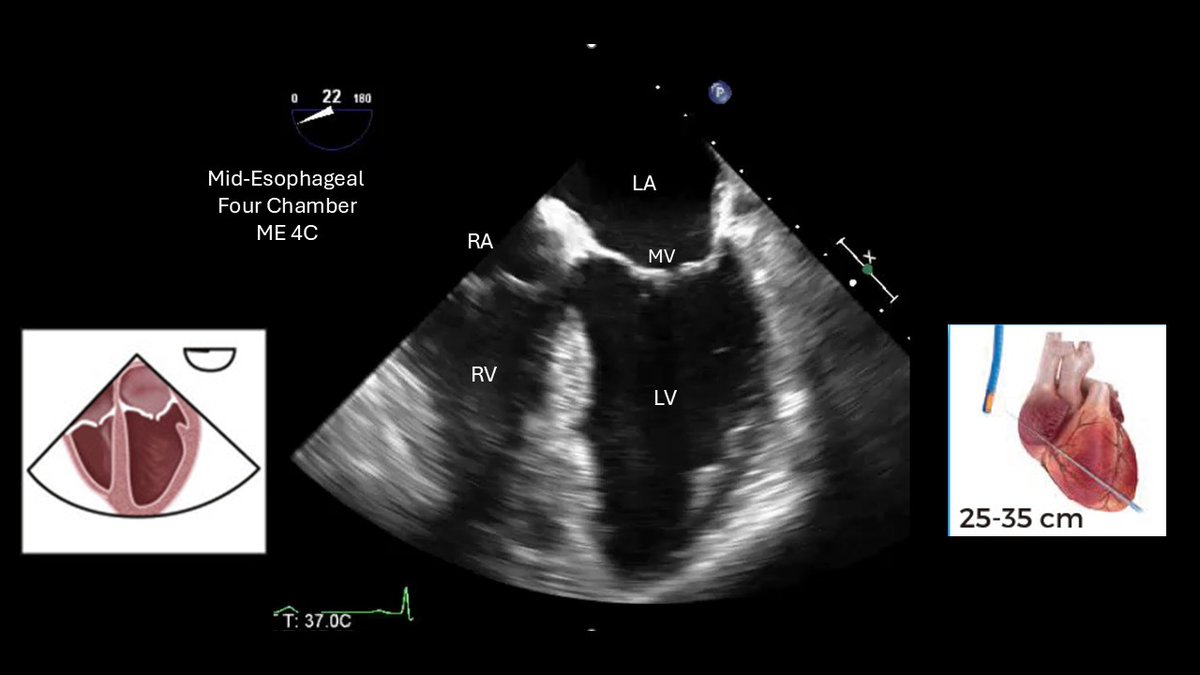

A suggested standard TEE examination. Basic probe positioning, manipulations, and views #cardiology #FOAMed #echocardio

11 Basic TEE Views

#useit #POCUS

Source: #supplementary-material" target="_blank" rel="nofollow noopener">onlinejase.com/article/S0894-…